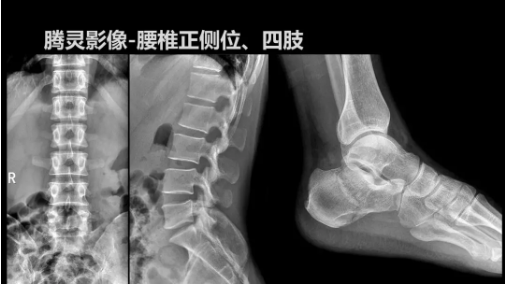

相較前代產(chǎn)品,“騰靈”在圖像質(zhì)量方面得到了全面升級,“騰靈”采用17*17非晶硅平板探測器設計,采集矩陣達3072*3072,動態(tài)范圍達16bit,為成像提供超大視野的同時保證成像質(zhì)量,此外,該款機型可根據(jù)醫(yī)療機構(gòu)的差異化需求而選配不同的動態(tài)平板探測器,以此來適應不同階層用戶所需。